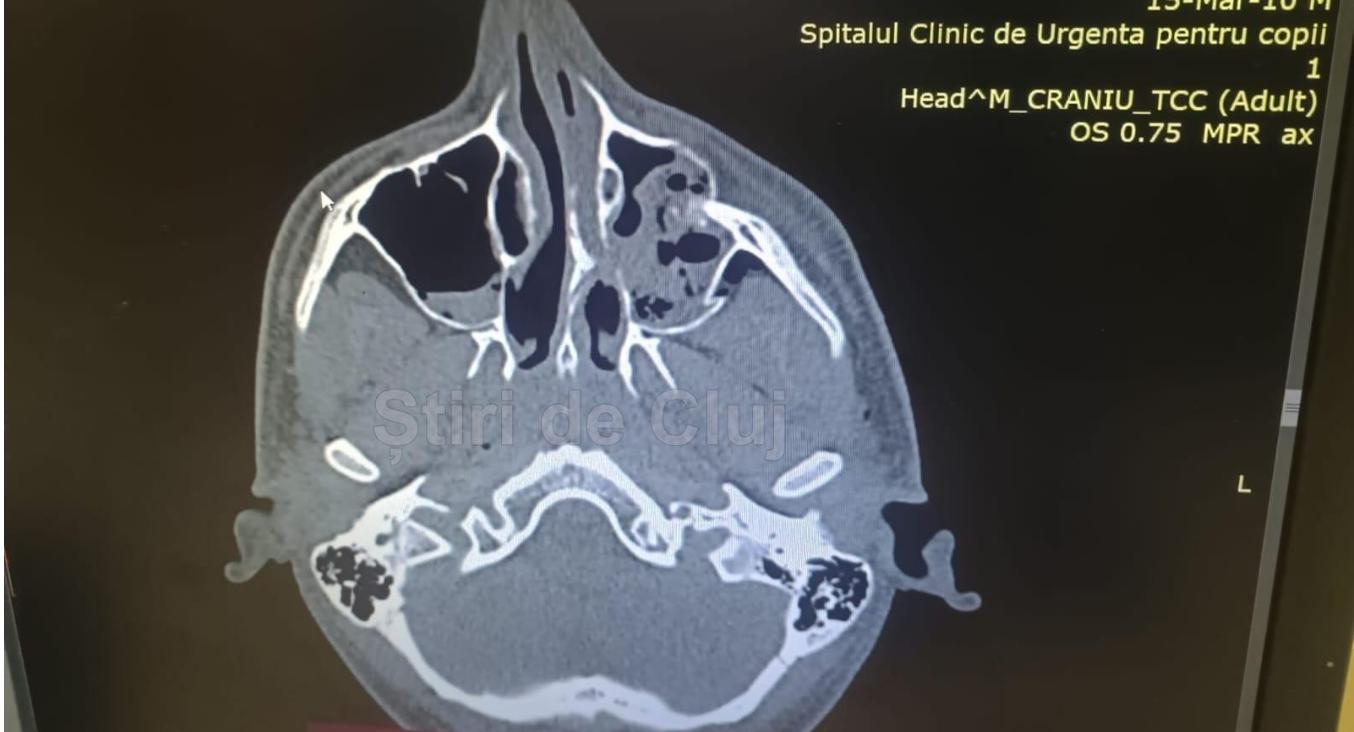

Diagnosticul medical a indicat:

fractura pereților sinusului maxilar stâng (cu excepția celui medial), cu infundare;

fractura peretelui lateral al orbitei stângi, cu ușoară încalecare;

hemosinus maxilar stâng, emfizem subcutanat și incluzii aerice intraorbitare;

deviație de sept nazal;

fără leziuni evidente la nivelul parenchimului cerebral.

Concluzia medicilor a fost clară: fracturi ale pereților sinusului maxilar stâng și ale orbitei stângi, leziuni care au impus intervenții chirurgicale complexe.